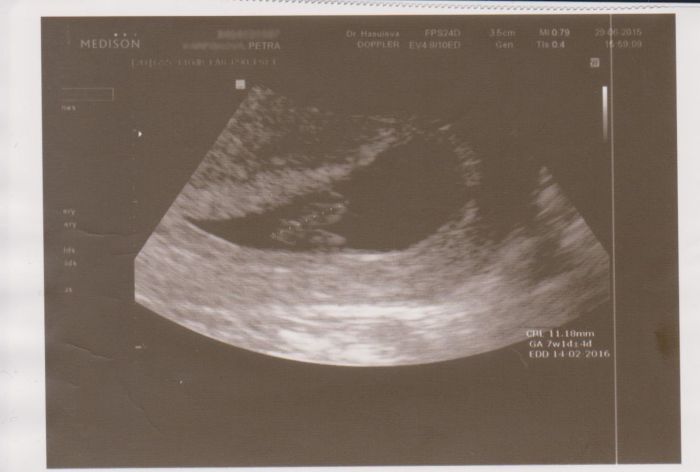

Ahoj holky, tak já mám po prohlídce, jsem nadšená :D :D. Něco úžasnýho :). Přikládám fotku, jsem 7+2, srdíčko tluče, jsem tak ráááááda :).